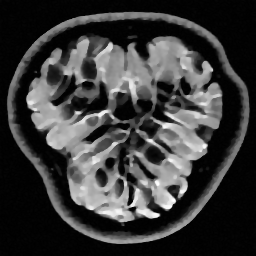

|

|

|

| Original image | Gauss. to DB4, err=31.54% | Gauss. to Flip DB4, err=31.51% |

|

|

|

| Subsampling pattern | DFT to DB4, err=10.96% | DFT to Flipped DB4, err=99.3% |

Since it will become important later, we now describe a quick and simple test, which we call the flip test, to investigate the presence or absence of an RIP. Success of this test suggests the existence of an RIP and failure demonstrates its lack.

Let be a sensing matrix, an image and a sparsifying transformation. Recall that sparsity of the vector is unaffected by permutations. Thus, let us define the flipped vector

and using this, we construct the flipped image Note that, by construction, we have . Now suppose we perform the usual compressed sensing reconstruction (1) on both and , giving approximations and . We now wish to reverse the flipping operation. Thus, we compute which gives a second approximation to the original image .

This test provides a simple way to investigate whether or not the RIP holds. To see why, suppose that satisfies the RIP. Then by construction, we have that

Hence both and should recover equally well. In the top row of Figure 1 we present the result of the flip test for a Gaussian random matrix. As is evident, the reconstructions and are comparable, thus indicating the RIP.

Having considered type II problems, let us now examine the flip test for a type I problem. As discussed, in applications such as MRI, X-ray CT, radio interferometry, etc, the matrix is imposed by the physical sensing device and arises from subsampling the rows of the DFT matrix .111In actual fact, the sensing device takes measurements of the continuous Fourier transform of a function . As discussed in BAACHGSCS ; BAGSAIEP , modelling continuous Fourier measurements as discrete Fourier measurements can lead to inferior reconstructions, and worse, inverse crimes. To avoid this, one must consider an infinite-dimensional compressed sensing approach, as in (2). See AHPRBreaking ; BAGSAIEP for details, as well as PruessmannUnserMRIFast for implementation in MRI. However, for simplicity, we shall continue to work with the finite-dimensional model in the remainder of this paper. Whilst one often has some freedom to choose which rows to sample (corresponding to selecting particular frequencies at which to take measurements), one cannot change the matrix .

It is well known that in order to ensure a good reconstruction, one cannot subsample the DFT uniformly at random (recall that the sparsifying transform is a wavelet basis), but rather one must sample randomly according to an appropriate nonuniform density AHPRBreaking ; Candes_Romberg ; Lustig ; WangAcre . See the bottom left panel of Figure 1 for an example of a typical density. As can be seen in the next panel, by doing so one achieves a great recovery. However, the result of the flip test in the bottom right panel clearly demonstrates that the matrix does not satisfy an RIP. In particular, the ordering of the wavelet coefficients plays a crucial role in the reconstruction quality. To explain this, and in particular, the high-quality reconstruction seen in the unflipped case, one evidently requires a new analytical framework.

Note that the flip test in Figure 1 also highlights another important phenomenon: namely, the effectiveness of the subsampling strategy depends on the sparsity structure of the image. In particular, two images with the same total sparsity (the original and the flipped ) result in wildly different errors when the same sampling pattern is used. Thus we conclude that there is no one optimal sampling strategy for all sparse vectors of wavelet coefficients.